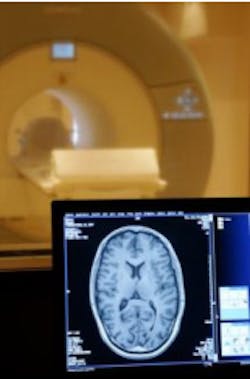

MRI scans show the distribution of the dye in the brain, enabling much smaller tumors to be detected than can be achieved using current techniques.